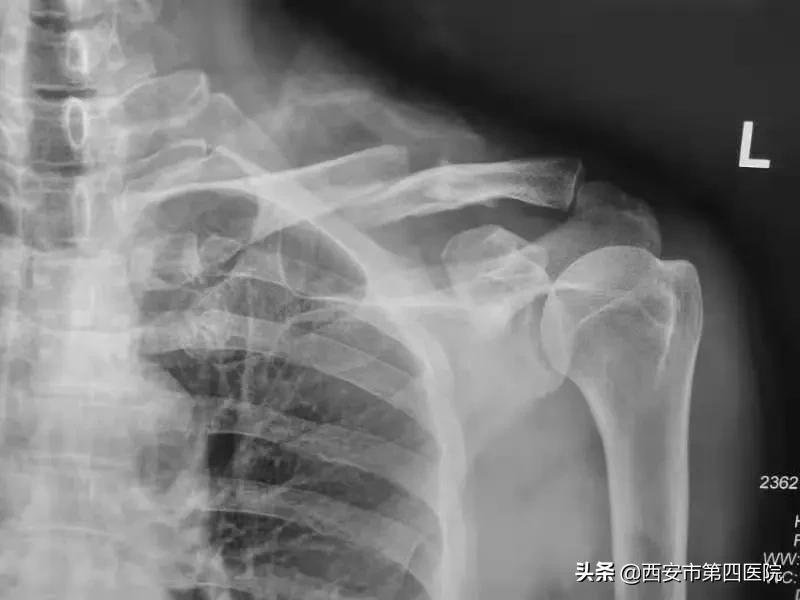

患者宋某,因摔倒致左侧肩关节疼痛伴活动障碍1天,去大差市院区就诊,姬海鹏副主任医师接诊,经过详细询问病史及体格检查后,考虑为左侧锁骨骨折,X线片结果证实了专家的诊断。与家属沟通并征得知情同意后,在医院领导及综合办的协助下,患者当天即入住航天城院区过渡病房。